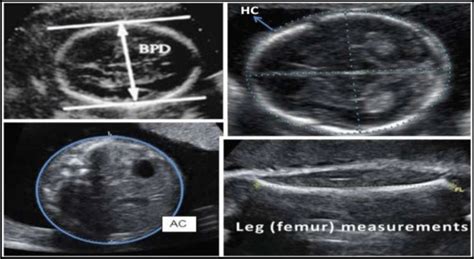

First up, we have the Biparietal Diameter , or BPD . This one is all about your baby’s head. Specifically, it measures the widest part of the fetal skull, from one parietal bone to the other, usually at a level that includes the thalami and the cavum septum pellucidum. Why is this important? Well, the BPD gives a good indication of the baby’s head circumference and growth. It’s one of the primary measurements used to estimate gestational age, especially in the second trimester. A consistent BPD measurement helps ensure the baby’s head is growing proportionally. It’s also a crucial marker when doctors are assessing for potential issues with fetal brain development or head shape abnormalities. When they’re looking at the BPD, they’re essentially measuring the width of the skull, which helps them gauge the overall size of the head. This measurement, along with others, contributes to the estimation of the baby’s age and expected delivery date. It’s fascinating how they can get such precise measurements from the outside, right? The BPD is a foundational measurement in assessing fetal head growth.

Head Circumference (HC)

Next, we have the Head Circumference , or HC . This measurement essentially circles around the baby’s head, following the same plane as the BPD. Think of it as the BPD’s broader cousin, giving a more comprehensive idea of the baby’s head size. The HC is calculated using the BPD and sometimes the occipitofrontal diameter (OFD) and is another vital parameter for assessing fetal growth and gestational age. A well-proportioned HC relative to other measurements suggests normal head development. If the HC seems significantly larger or smaller than expected based on gestational age, it can prompt further investigation into potential conditions like microcephaly (abnormally small head) or macrocephaly (abnormally large head), or even issues related to fetal brain development. It’s all about ensuring that the head is growing at a rate that aligns with the rest of the baby’s body. The HC provides a circumferential view of fetal head growth.

Abdominal Circumference (AC)

Now, let’s move down to the Abdominal Circumference , or AC . This measurement is exactly what it sounds like: it measures the circumference of the baby’s abdomen at a specific level, usually encompassing the stomach, the umbilical vein, and the left portal vein. Why focus on the tummy? Because the baby’s abdominal growth is heavily influenced by factors like the liver and intestines, which are crucial for fetal nutrition and growth. The AC is a really important indicator of fetal weight and growth, especially in the later stages of pregnancy. It helps doctors assess if the baby is receiving adequate nutrition and growing appropriately. Discrepancies in AC compared to other measurements might suggest issues with placental function, fetal nutrition, or certain fetal conditions affecting the liver or other abdominal organs. The AC is a key indicator of fetal weight and nutritional status. It’s where the magic of nutrient absorption and processing happens, so its growth is super telling.

Femur Length (FL)

Finally, we have the Femur Length , or FL . This one is pretty straightforward: it measures the length of the baby’s femur, which is the thigh bone. It’s the longest bone in the body and a very reliable indicator of skeletal growth. The FL measurement is particularly useful for estimating gestational age and assessing skeletal development. Since long bones tend to grow at a predictable rate, the FL is less affected by factors like amniotic fluid levels or maternal abdominal fat compared to circumference measurements. A normal FL measurement, when correlated with BPD and AC, helps confirm the overall growth pattern. Significant deviations in FL might raise concerns about skeletal dysplasia (disorders affecting bone and cartilage) or other growth abnormalities. The FL is a crucial measure of fetal long bone and skeletal growth. It gives us a peek into how the baby’s